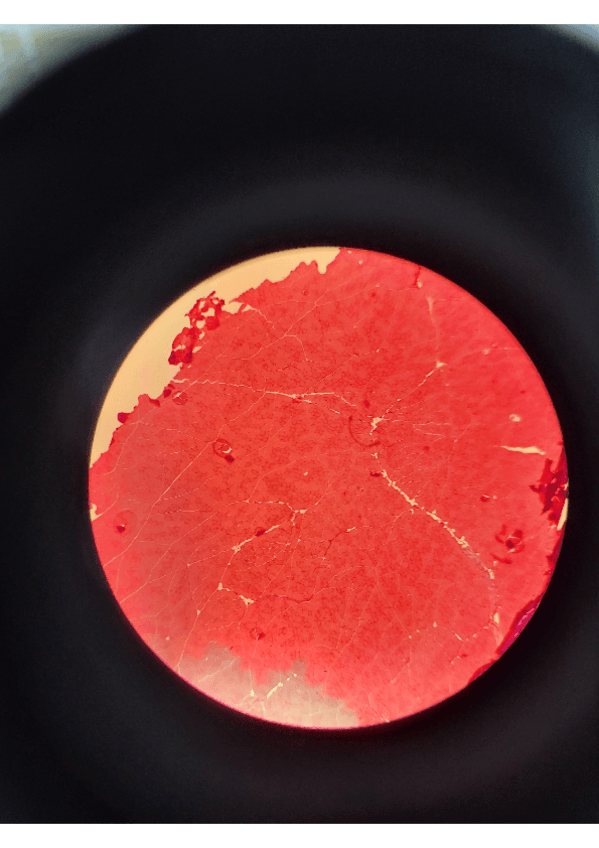

En el documento, se encuentran explicadas las imágenes para comprenderlas bien. Además de esto, en algunas muestras se incluye un recuadro en el que aparece lo que hay que poner en el examen, según dijeron los profesores durante las prácticas.

He publicado nuevos practicas de 1º Histología Médica I: Portafolio-Practicas-Histologia.pdf

He publicado nuevos practicas de 1º Histología Médica I: Imagenes-Practica-5-Histologia-1.pdf

He publicado nuevos practicas de 1º Histología Médica I: Imagenes-Practicas-3-4-Histologia-1.pdf